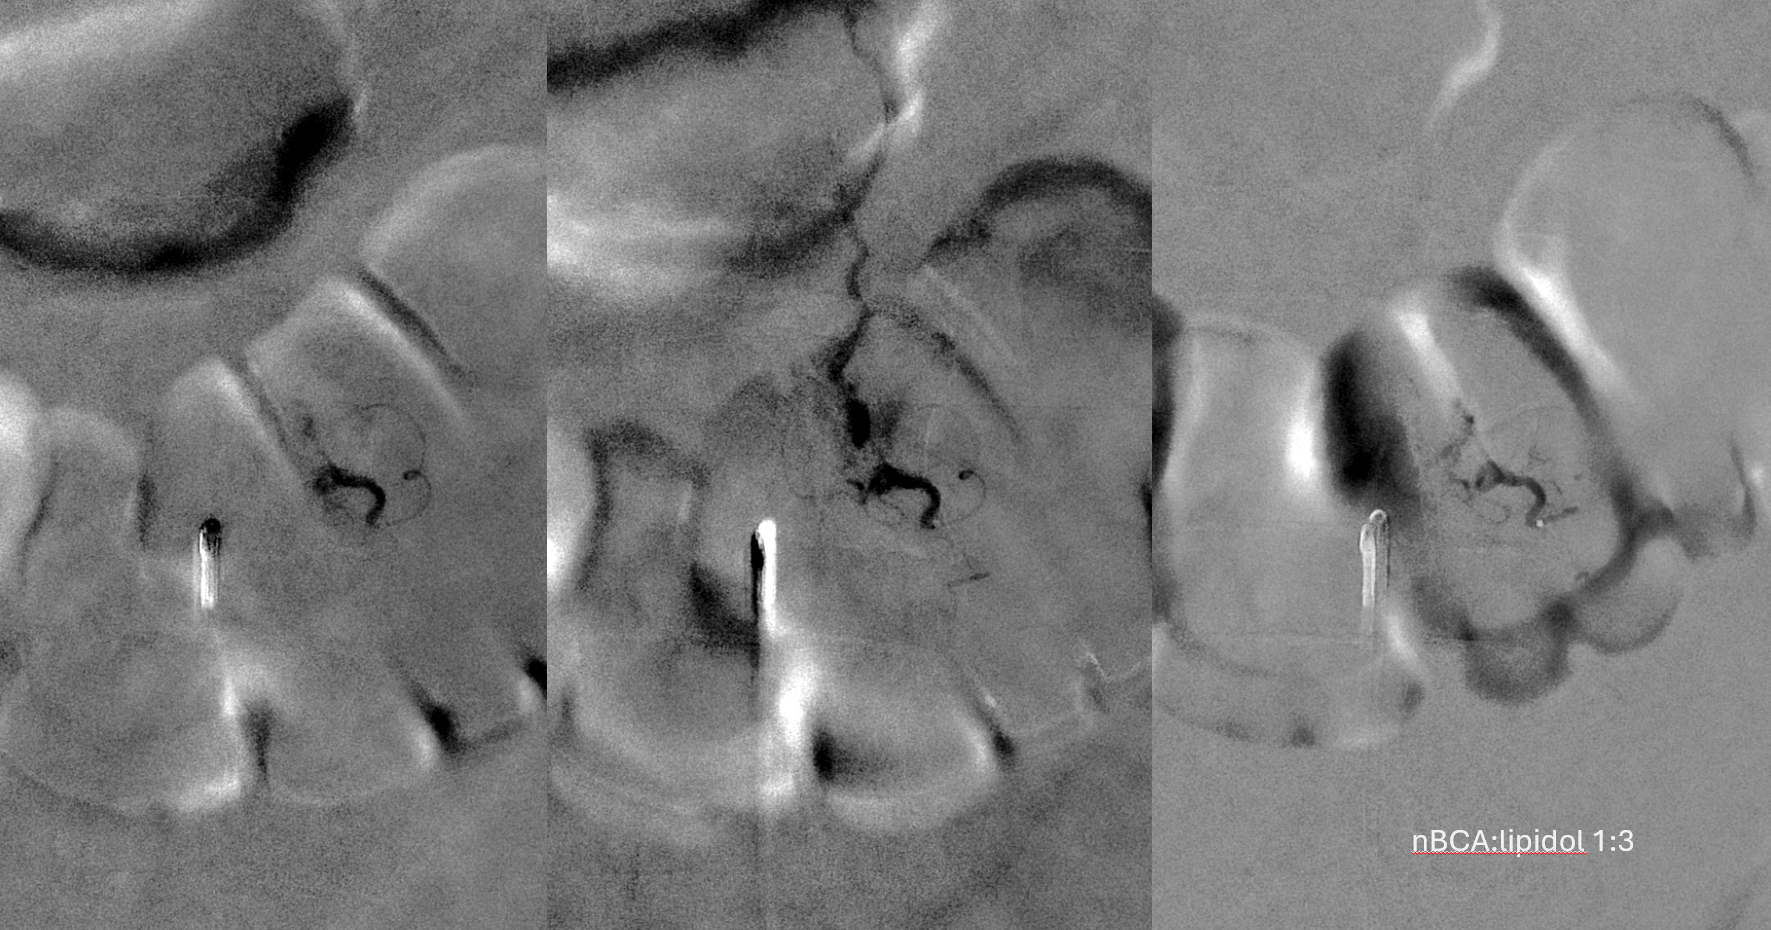

Headway duo near fistula. There are several other inflows, and the position is not optimal

Below is a better position. The fistula is at the level of the ball of vessels above the microcatheter tip. Several tributaries are present, which is not great, as they will tend to polymerize nBCA before it reaches the vein. Fortunately the radicular venous segment is long, before it reaches cord surface veins, so there is a lot of safety. This is not the case with upper thoracic fistulas, and we don’t want to spill glue into cord surface veins. It promotes thrombosis, which is erroneously known as the Foix-Alajouanine syndrome. The actual syndrome was described by Foix and Alajouanine as the clinical end stage of untreated spinal dural fistulas — ascending paralysis, followed by respiratory dysfunction, aspiration, and death. It was not an iatrogenic problem. The name was adopted to describe post-treatment acute deterioration due to thrombosis of enlarged cord veins after closure of the fistula and reduction of venous flow, in part because clinical presentation is comparably horrible. Typically happens some 6-12 hours after treatment, and almost always within 24 hours. Treatment is with aggressive emergent anticoagulation, and outcome is variable.

A 1:2 nBCA:lipidol dilution was chosen because of additional arterial inflows over which we had limited control (we usually use 1:1). Result seems good

Not so fast. Fistula still alive — which is exceptionally rare after putting this much glue into the vein. Yes, glue is diluted but still its plenty. There is also heparin on board — we pre-treated given massive venous congestion and concern for thrombosis. Still, this is extremely rare. Much slower, but still alive. It is a mistake to hope it thromboses later. Very likely it will not, and hoping it will only contributes to the reputation that endovascular is less effective than surgery.

Re-catheterization (left and center) and additional nBCA injection — even more dilute now that the vein outflow is relatively protected. We think this is good now.